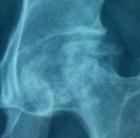

股骨頭囊變

-早期表現 出現股骨頭囊性變,由於外傷,潛水病,服用激素,酗酒等引起股骨病變,但並沒有缺血壞死.股骨頭囊變

治療比較困難沒有特效藥物,查明壞死和囊變的原因,根據不同原因治療,平時多注意不要大幅度運動

遵從醫生安排,生活上減少負重,行動時扶杖,可行髖關節軟組織松解術,以減輕關節內壓力,防止塌陷,必要時手術治療.

如果不影響正常生活可以不做治療,但須注意過度負重.影響正常生活可考慮手術切除

早期可以採用保守的方法治療,晚期則需要手術治療